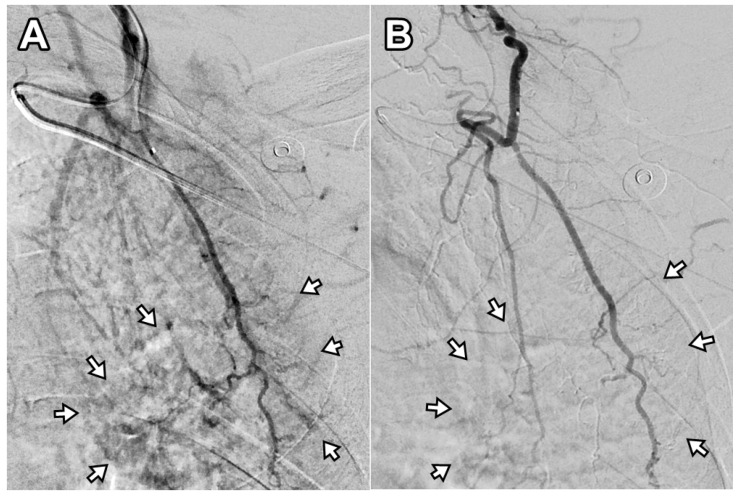

Objective: Chronic non-cervical-origin interscapular pain remains challenging to treat when refractory to conservative management and ultrasound-guided injections. This retrospective feasibility study aimed to assess the feasibility, procedural practicality, safety, and preliminary clinical outcomes of transarterial embolization (TAE) as a salvage therapy in this patient population. Methods: This single-center retrospective study included 20 patients with chronic interscapular pain (Numeric Rating Scale [NRS] score ≥5 for >3 months) who initially underwent ultrasound-guided injection therapy. Patients who experienced inadequate pain relief after 3 months (n = 10) proceeded to TAE, while the remaining 10 patients with sufficient relief formed the comparison group. TAE primarily targeted the transverse cervical artery using imipenem/cilastatin sodium as the embolic agent. Pain outcomes were assessed using NRS scores at 1, 3, and 6 months post-procedure. The primary outcome was pain reduction (≥50% decrease in NRS score), with secondary outcomes including technical success, medication use, and safety assessment. Results: The mean baseline NRS score for all patients was 6.5 ± 1.4, which decreased to 3.4 ± 2.0 at 1 month and 3.9 ± 2.5 at 3 months post-injection (p < 0.001). In the TAE group, the NRS score decreased from 7.4 ± 1.4 to 5.1 ± 1.1 at 1 month and 6.0 ± 1.4 at 3 months, indicating inadequate pain relief. In contrast, the injection-only group showed significant improvement, with NRS scores decreasing from 5.6 ± 0.5 to 1.6 ± 0.5 at 1 month and 1.7 ± 0.7 at 3 months (p < 0.001). The reduction in NRS scores was significantly less in the TAE group compared with the injection-only group (-2.2 vs. -4.0 and -28.7% vs. -71.4% at 1 month; -1.4 vs. -3.9 and -18.2% vs. -69.7% at 3 months; all p ≤ 0.001). Following TAE, the mean NRS score further decreased to 2.1 ± 0.7, 2.0 ± 1.1, and 1.9 ± 1.2 at 1, 3, and 6 months, respectively (p < 0.001), with clinical success rates of 90%, 100%, and 90% at these respective time points. At the final follow-up, the percentage of NRS score reduction was comparable between the TAE and injection-only groups (-74.8% vs. -69.7%, p = 0.397). No severe or life-threatening adverse events were observed; only self-limited adverse events were reported. Conclusions: In this retrospective feasibility study, TAE appeared safe and effective as a salvage therapy for patients with refractory non-cervical-origin interscapular pain unresponsive to injection therapy. Further prospective, randomized studies are needed to validate these findings, refine patient selection criteria, and optimize treatment outcomes.